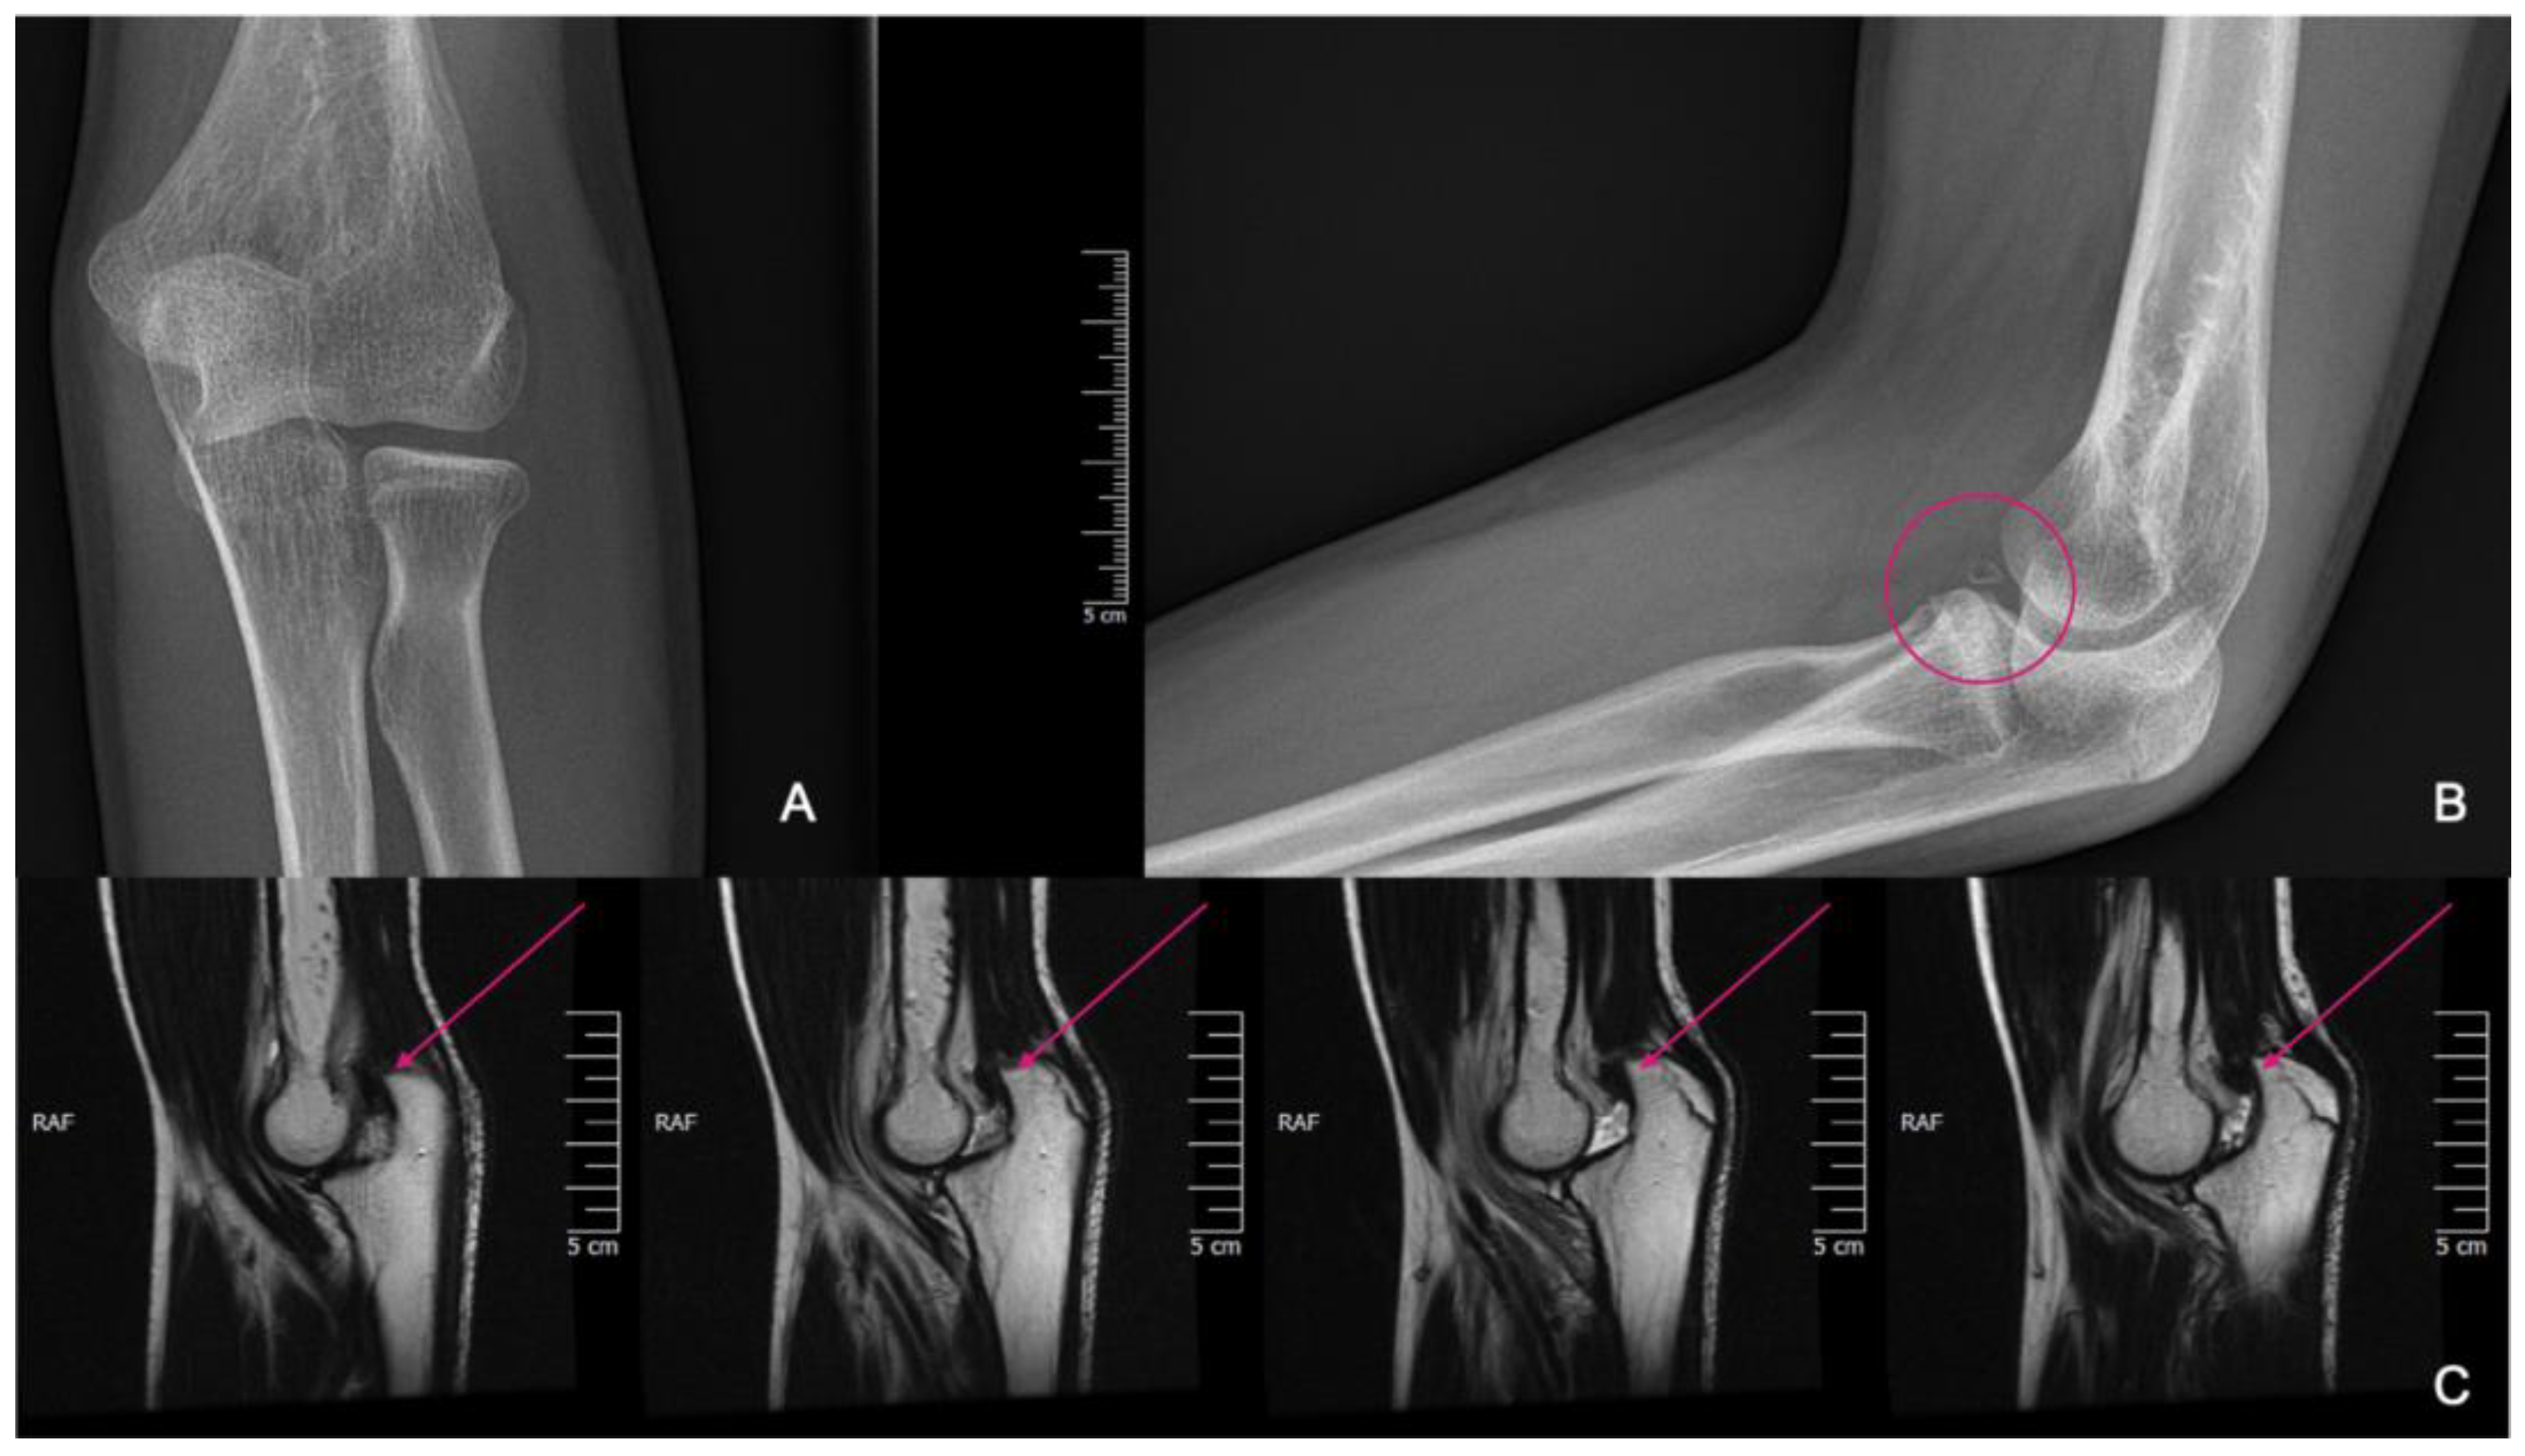

He suffered another elbow trauma due to a fall at the age of 14, resulting in pain and dislocation. X-rays showed no recent fracture, but a 5 mm rounded bone fragment was visible. MRI was requested for diagnostic purposes and further exploration (Figure 6). The results indicated that the fragment originated from the coronoid process and that the elbow was in a dorsally subluxated position. With regard to the instability, the exploration of the joint with debridement and reconstruction was proposed. A CT scan was performed for surgical planning, which yielded equivalent results to the MRI. A summary of events can be seen in Table 2.

Figure 6. X-rays showing fragmentation, highlighted by the pink circle (A,B). Subluxation is visible on the MRI pointed at with pink arrows (C).